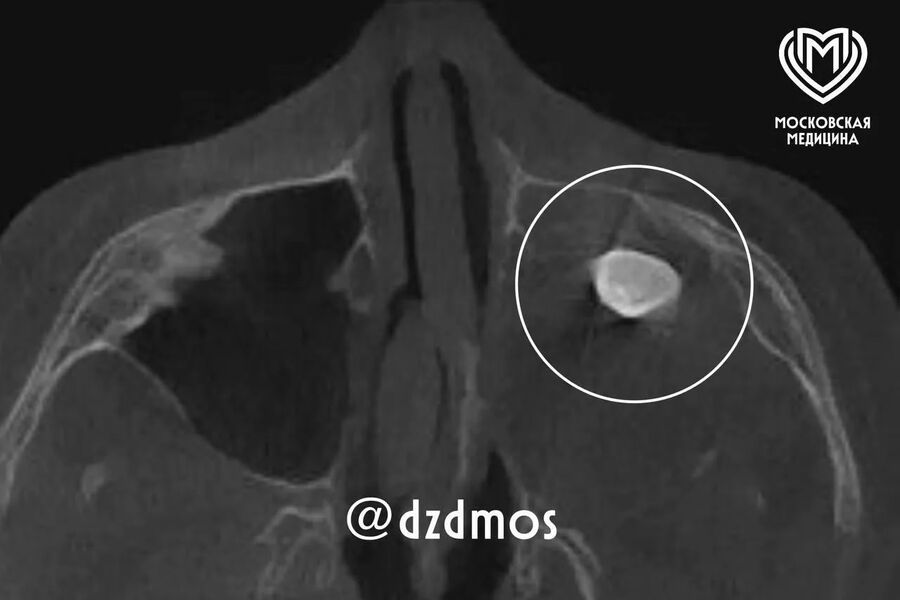

Московские врачи удалили подростку зуб, выросший в носу

Депздрав: врачи Филатовской больницы удалили подростку зуб, выросший в носу

Врачи Филатовской больницы в Москве удалили подростку зуб, который вырос в носу. Об этом сообщает столичный депздрав в своем канале в Max.

Уточняется, что 15-летний мальчик попал в больницу с жалобами на асимметрию лица и заложенность носа. До этого, как отметили в депздраве, мальчика осматривали врачи частной клиники — они нашли в гайморовой пазухе сформировавшийся зуб и предложили удалить его.

Родители подростка решили выслушать второе мнение и обратились за консультацией в Филатовскую больницу, где по результатам консилиума врачи предложили провести операцию по Колдуэллу-Люку, то есть обеспечить доступ через верхнюю десну, чтобы вернуть ему возможность нормально дышать.

Сделав разрез, врачи обнаружили новообразование, внутри которого и находился зуб, рассказал хирург-оториноларинголог Вугар Достиев. По его словам, доброкачественная опухоль оказалась тератомой — эмбрионально-клеточным новообразованием, внутри которого могут находиться элементы тканей, несвойственные этому участку тела.

Достиев уточнил, что после восстановления функций подростка выписали с хорошим самочувствием, также постепенно асимметрия его лица и заложенность носа полностью исчезли.